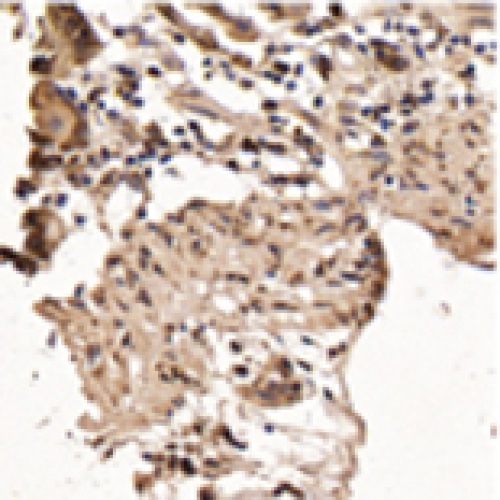

13 Nov 2018 : Laboratory Research

Expression and Molecular Regulation of the Cox2 Gene in Gastroenteropancreatic Neuroendocrine Tumors and Antiproliferation of Nonsteroidal Anti-Inflammatory Drugs (NSAIDs)

Feng Gao, Mohammad Ishraq Zafar

DOI: 10.12659/MSM.912419

Med Sci Monit 2018; 24: LBR8125-8140